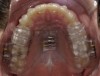

Fig 8. The appliance worn during treatment, anterior view (Fig 8), right side view (Fig 9), left side view (Fig 10), and upper arch view (Fig 11).

Figure 8

Fig 9. The appliance worn during treatment, anterior view (Fig 8), right side view (Fig 9), left side view (Fig 10), and upper arch view (Fig 11).

Figure 9

Fig 10. The appliance worn during treatment, anterior view (Fig 8), right side view (Fig 9), left side view (Fig 10), and upper arch view (Fig 11).

Figure 10

Fig 11. The appliance worn during treatment, anterior view (Fig 8), right side view (Fig 9), left side view (Fig 10), and upper arch view (Fig 11).

Figure 11

Intraoral scans were taken to document the patient's entire palate and bite registration. Scans were sent to the clinical team for the fabrication of a clear aligner/sleep appliance for the patient to wear; the chosen appliance fits over clear aligners, regardless of the tray number the patient may need (Figure 7 through Figure 11).

After the appliance was delivered, additional photographs were taken with the camera to ensure that the appliance was delivered as intended, to document the case, and to show the patient the ideal fit of the appliance in his mouth as instructions were reviewed with him.